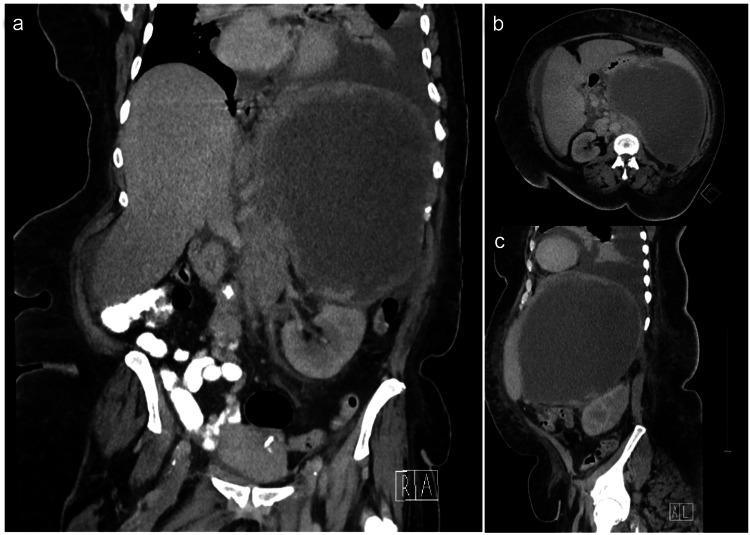

Diffuse large B-cell lymphoma (DLBCL) is the most common type of non-Hodgkin lymphoma. Though the presentation is diverse, patients typically have a history of "B" symptoms and lymphadenopathy in areas such as the neck, mediastinum, or abdomen. However, a growing body of evidence suggests DLBCL can present as a cystic mass in diverse tissues. We present the case of a large cystic left retroperitoneal mass of unknown origin in a patient subsequently diagnosed with DLBCL. The diagnosis was obtained via percutaneous biopsy of the cystic mass in preparation for surgical excision. Upon diagnosis, surgical intervention was aborted, and the patient was started on chemotherapy treatment. However, four weeks into her treatment, she slipped and fell while in the bathroom and presented to the emergency department in shock with a computed tomography (CT) scan suggestive of splenic rupture. She underwent emergent splenectomy and resection of the cystic mass. She was discharged on postoperative day 7 and is currently continuing with outpatient chemotherapy. The presentation of DLBCL is notoriously diverse, however, this patient represents a unique presentation that adds to a growing body of literature suggesting DLBCL can present as a cystic mass. Pathological diagnosis should be obtained in all patients with cystic lesions of unknown origin before any surgical intervention to avoid unnecessary surgery and provide an optimal management plan.